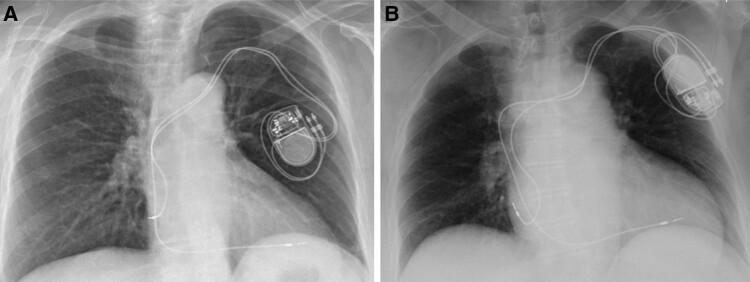

This report describes two clinical cases that occurred in our centre, for which two different solutions were successfully implemented. In the first case, a complete removal of the stimulation system was performed, and a leadless pacemaker (PM; Medtronic Micra VR) was implanted. In the second case, the patient underwent a revision procedure. The PM was disconnected, and the electrodes were debrided, a submuscular pocket for the PM was created, and at the end of the procedure, the PM was anchored to the pectoralis major.

Twiddler syndrome is a not so rare and serious complication of CIED implantation, leading to device malfunctioning and higher risk of infection of the pocket due to multiple re-interventions. In these two cases, different surgical solutions were performed, both resulting to be effective to solve the effects of TS.